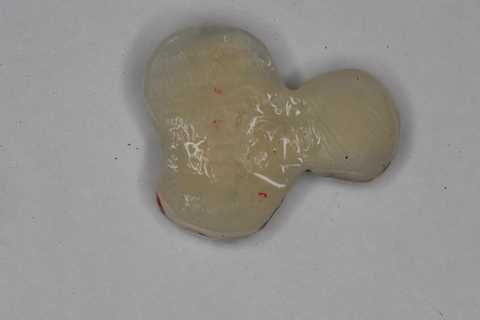

今日の抜歯再植術シリーズ35.3 2025.11.19

今日の抜歯再植術シリーズ39.3 2025.11.16

今日の抜歯再植術シリーズ39.2 2025.11.15